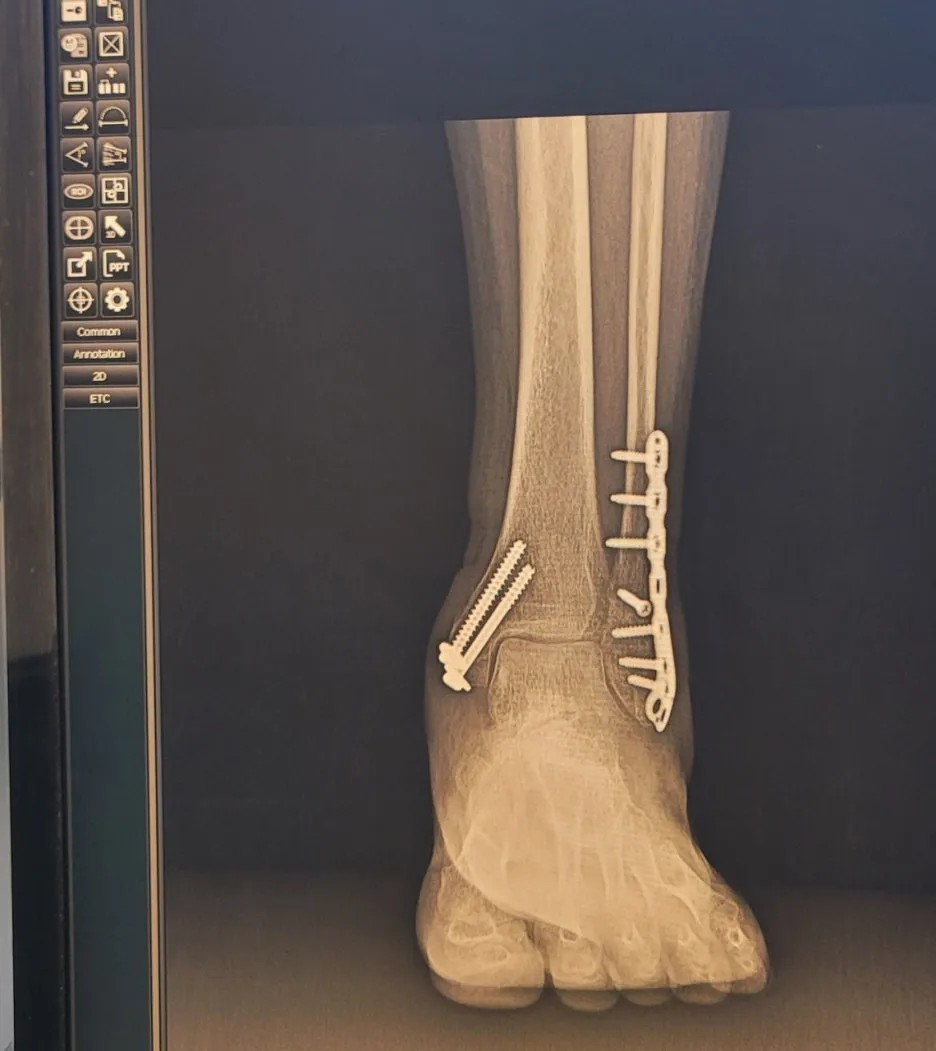

발목골절 x레이, 왼쪽 발

13주에 병원에 검진 갔더니

조깅을 천천히 하라더군요.

뼈가 3개월 정도면 붙는다면서요.

이제부터는 2개월마다 검진,

내년 5월 철심을 빼는 수술을

하자고 하더군요.